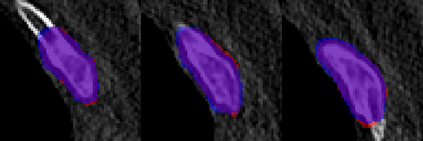

Rib fractures are a common and potentially severe injury that can be challenging and labor-intensive to detect in CT scans. While there have been efforts to address this field, the lack of large-scale annotated datasets and evaluation benchmarks has hindered the development and validation of deep learning algorithms. To address this issue, the RibFrac Challenge was introduced, providing a benchmark dataset of over 5,000 rib fractures from 660 CT scans, with voxel-level instance mask annotations and diagnosis labels for four clinical categories (buckle, nondisplaced, displaced, or segmental). The challenge includes two tracks: a detection (instance segmentation) track evaluated by an FROC-style metric and a classification track evaluated by an F1-style metric. During the MICCAI 2020 challenge period, 243 results were evaluated, and seven teams were invited to participate in the challenge summary. The analysis revealed that several top rib fracture detection solutions achieved performance comparable or even better than human experts. Nevertheless, the current rib fracture classification solutions are hardly clinically applicable, which can be an interesting area in the future. As an active benchmark and research resource, the data and online evaluation of the RibFrac Challenge are available at the challenge website. As an independent contribution, we have also extended our previous internal baseline by incorporating recent advancements in large-scale pretrained networks and point-based rib segmentation techniques. The resulting FracNet+ demonstrates competitive performance in rib fracture detection, which lays a foundation for further research and development in AI-assisted rib fracture detection and diagnosis.